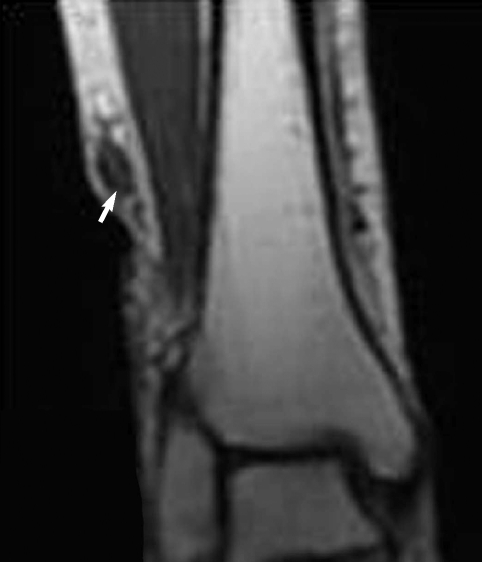

A 60-year-old woman living in Cheonan-si, Chungcheongnam-do, Korea, was admitted to Dankook University Hospital due to pain of the right ankle, aggravated on dorsiflexion. She had noticed a nodular mass at the medial side of the right knee 20 years ago, moving up and down very slowly. She went without any medical care for the lesion, and the mass was not notified for a long time. Three months ago, the mass was found again at the ankle of the patient, developing her ankle pain. On physical examination, an oval, rubber-like mass was found at just proximal to the lateral malleolus of the right foot. The mass was soft, non-tender, and 3 cm in diameter. In addition, another mass was found at the anterior part of the right ankle, and this produced discomfort on dorsiflexion. Routine laboratory tests were unremarkable and no eosinophilia was noted. The plain radiograph of the right leg revealed multiple calcifications extending from the medial part of the knee to the calf (Fig. 1), but nothing was found around the ankle joint. On the MR imaging, heterogeneous signals were observed in the mass, especially near the lateral malleolus (Fig. 2). Epidermoid cyst or dermatomyositis was suspected, and an operation was done on the mass.